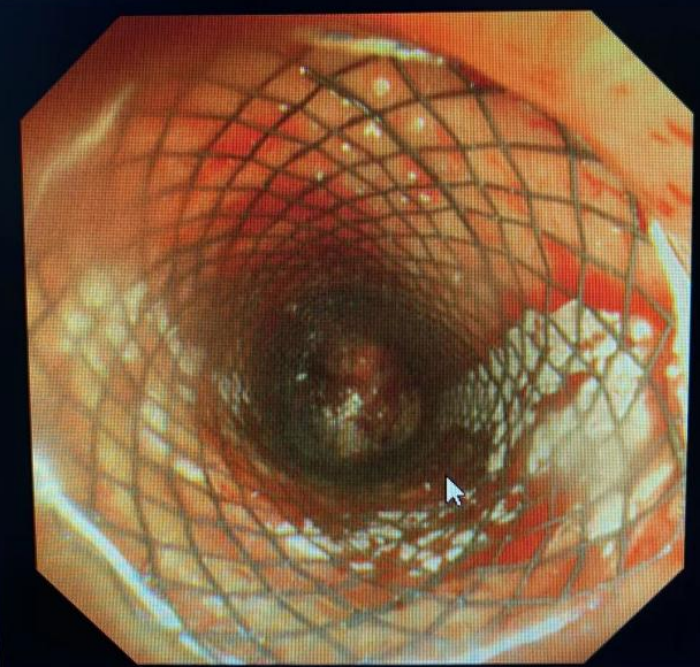

术后气道狭窄瞬间解除,支架位置良好

经过术前的细致准备及术中各个环节的无缝衔接,在吴西雅、梁莹及护理团队的默契配合下,在对气道肿瘤及分泌物进行清除后,气道Y型覆膜支架顺利在单导丝的引导下精准“落户”。整个手术过程约40分钟。术后患者胸闷、气促的症状明显缓解,提高了患者的生活质量,为进一步肿瘤治疗延长了宝贵的时间。